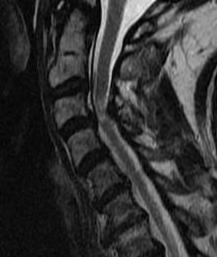

4. Evidence of cord edema / spinal cord damage

- often seen after acute injury in setting of stenosis

- best seen on STIR MRI

Spinal cord edema / injury